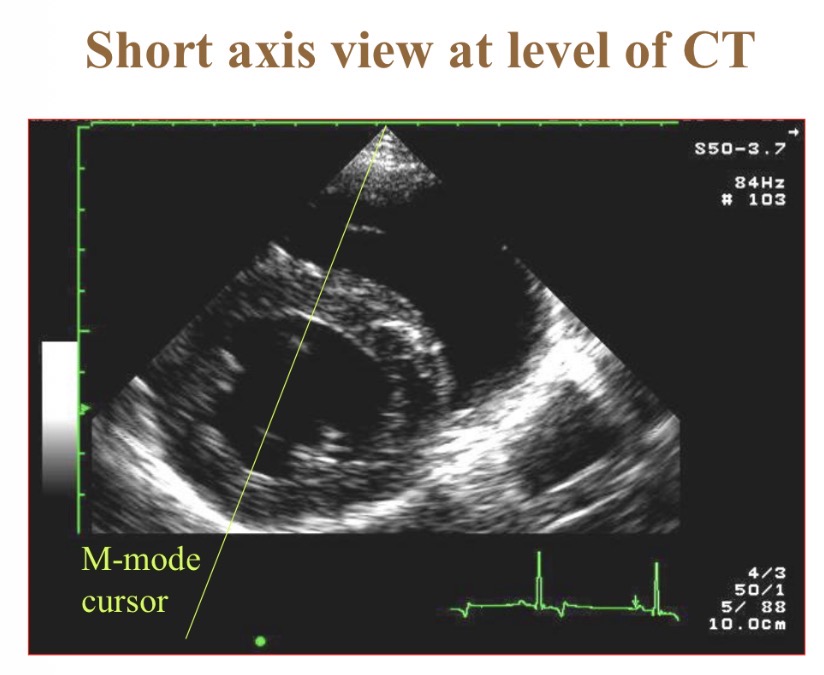

Short axis view

Levels of short axis views - a

Papillary

Levels of short axis views - B

Mitral

Levels of short axis views - C

Aortic

Levels of short axis views - D

LV

What level is at widest part of heart

Chordae tendinae

What does M-mode echocardiography show

Wall thickness/position over time/ ECG